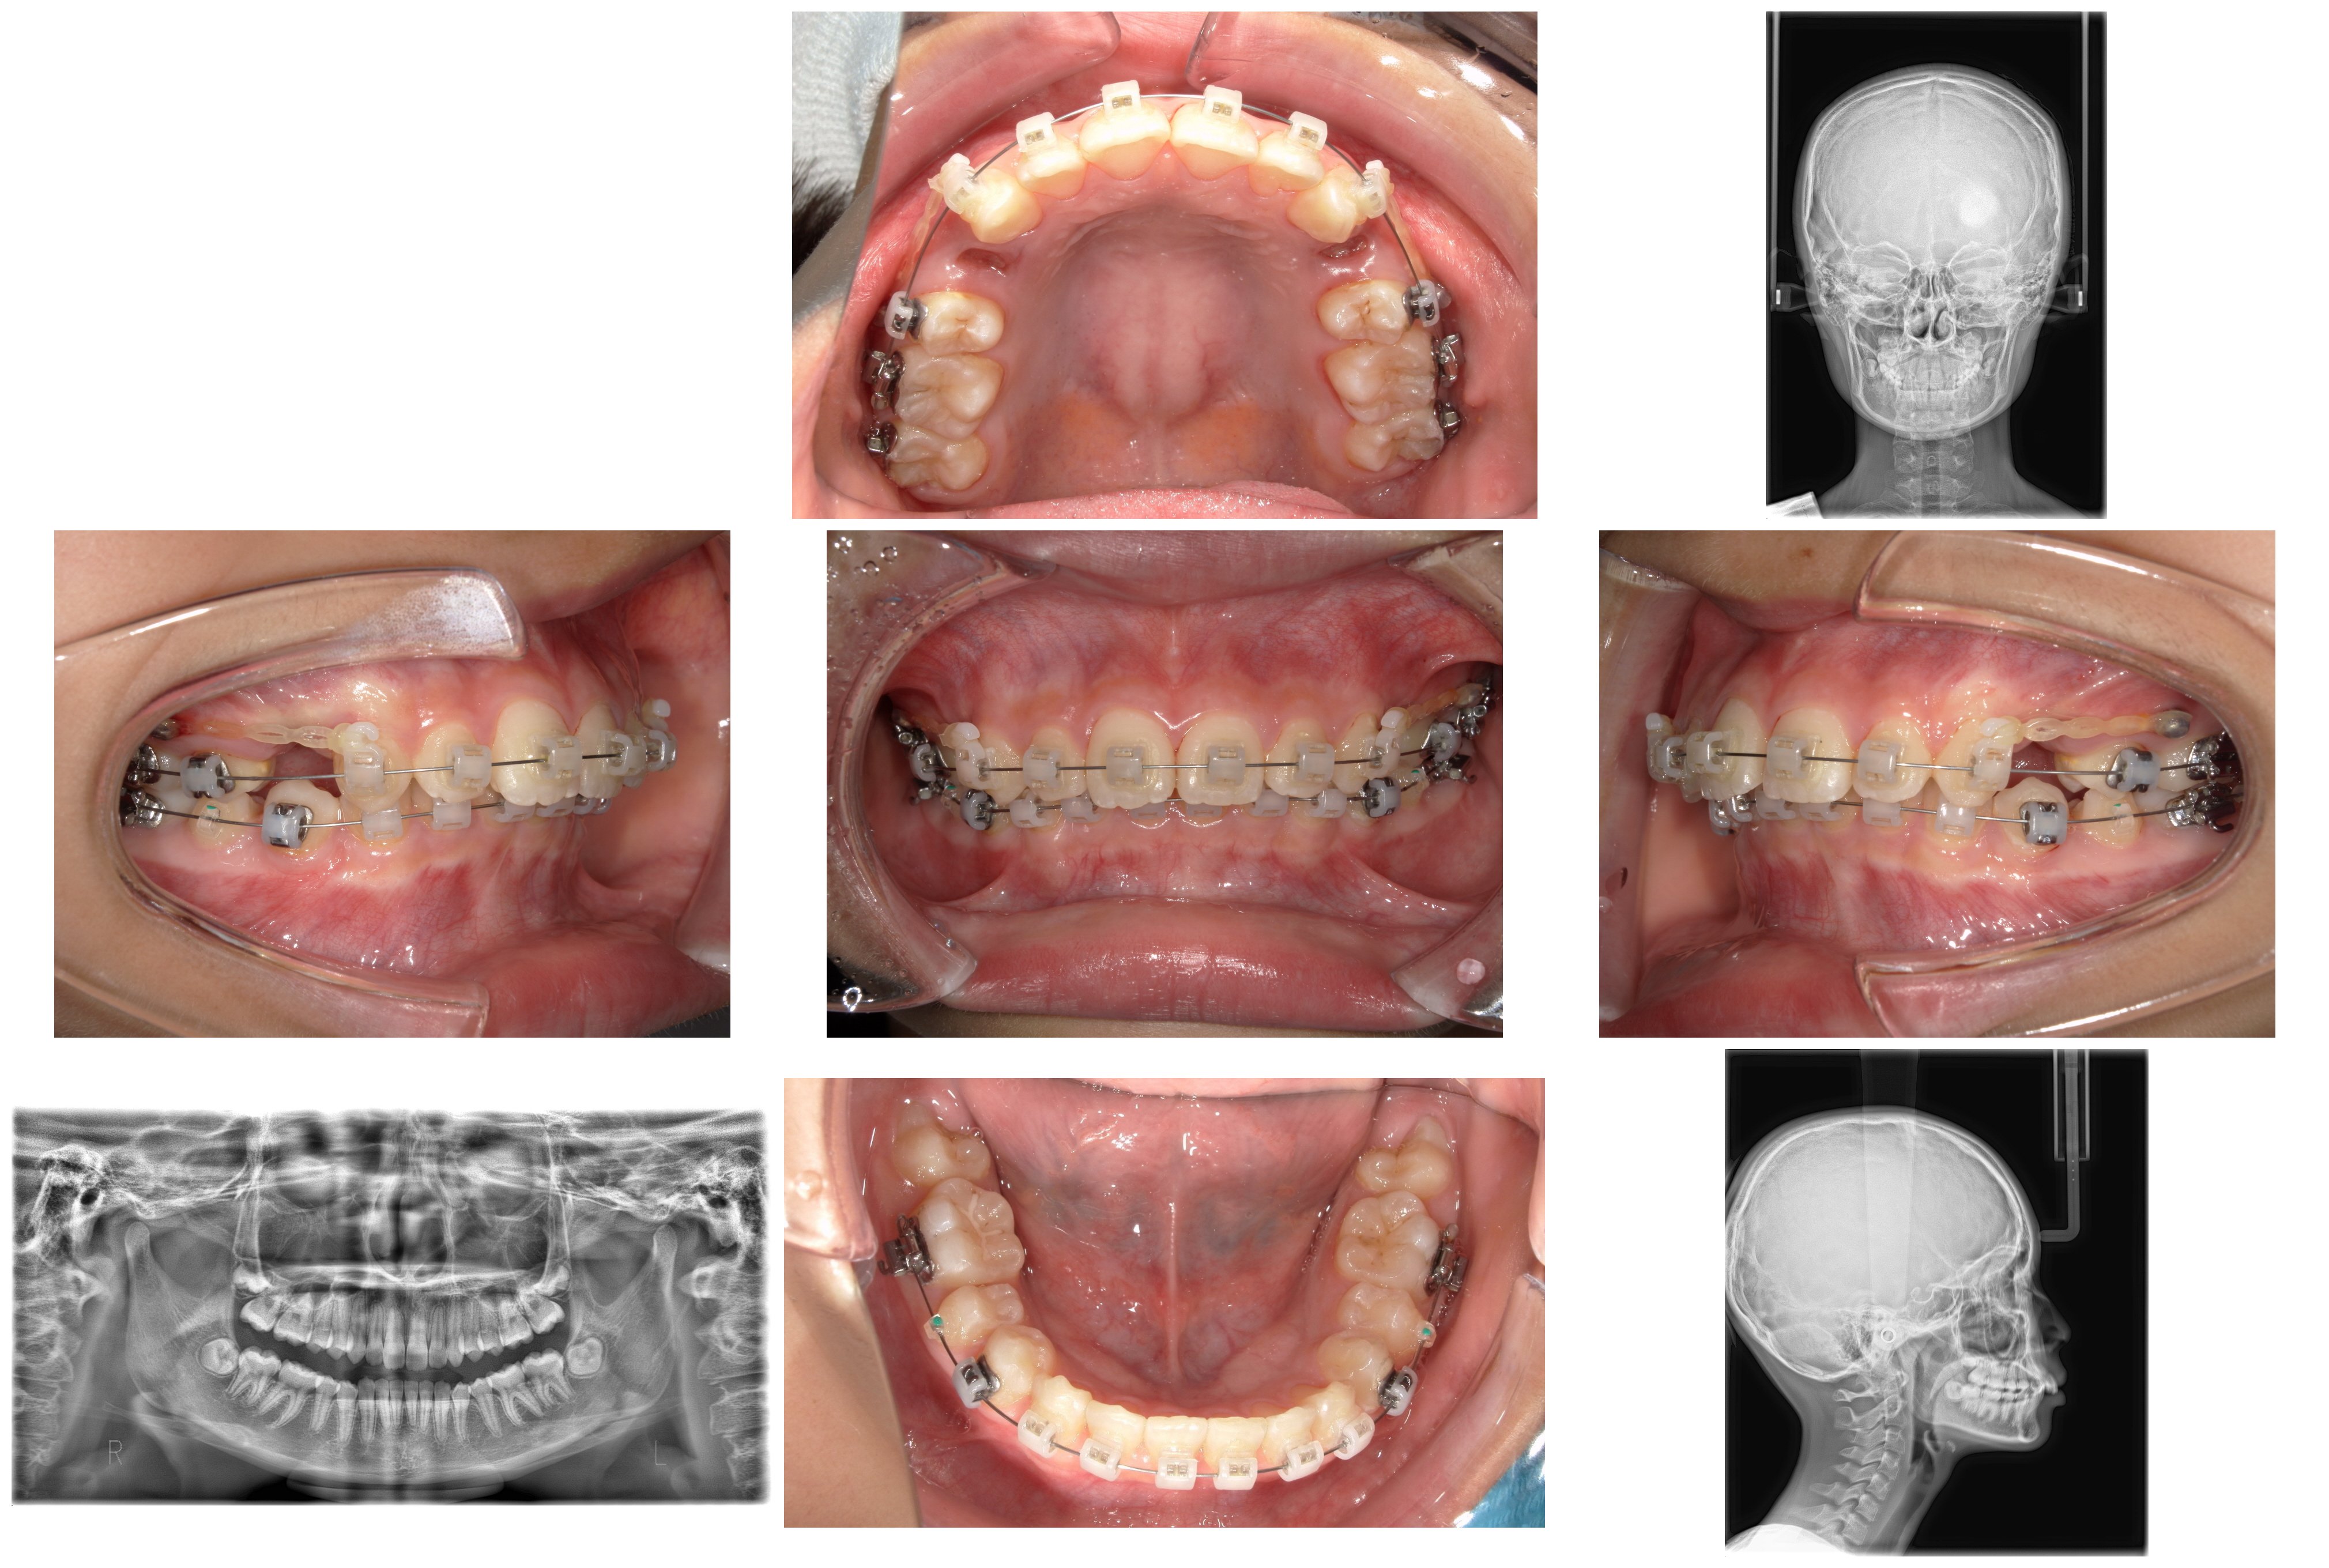

①装置装着~4か月後:咬み合わせの土台作り

まずは犬歯を後ろへ移動させるとともに、深い咬み合わせ(過蓋咬合)を改善するため、下顎にワイヤーを2本用いる手法で、前歯を押し下げて咬み合わせを浅くすることで咬合挙上(こうごうきょじょう)を図りました。

②装置装着8か月後:レジンマウントによる挙上

さらに下顎の奥歯に「レジンマウント(プラスチックの盛り物)」を装着し、咬み合わせの高さ(咬合高径)を強制的に確保しました。これにより、歯が動く際の邪魔な干渉を取り除きます。

③装置装着1年1か月後:こだわりのタイミングでの抜歯

この段階で、事前に根管治療を終えていた下顎左右の5番を抜歯しました。 一般的な矯正では治療開始前に抜歯しますが、本症例では「先に噛み合わせの高さを改善することを優先した」ため、あえてこの時期に抜歯を行いました。